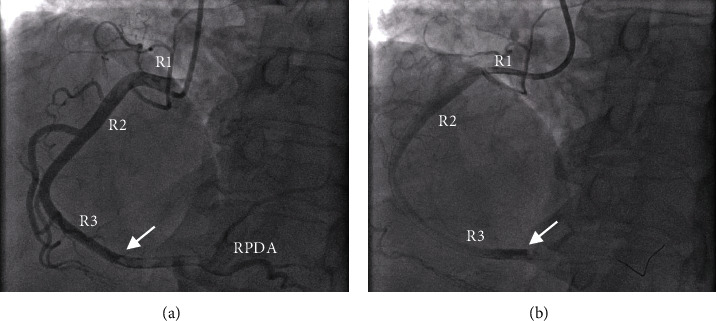

A 67-year-old woman with pulmonary hypertension (PH) presented with a 1-day history of worsening shortness of breath and pleuritic chest pain and was found to have a troponin T level of 3755 ng/L (ref. range 0-19 ng/L). An initial diagnostic workup in the emergency department (ED) led to an urgent left heart catheterization which revealed a 90% occlusive right coronary artery blood clot, even though a recent heart catheterization less than a month prior was completely unremarkable. Further workup led to the discovery of a patent foramen ovale (PFO) and an aneurysmal interatrial septum, suggesting the presence of a paradoxical embolism. While typically asymptomatic, a PFO is an important clinical entity that can lead to irreversible cardiac damage. Suspicion should be high for this finding in the case of an acute myocardial infarction (MI) with no clear cause, especially in a patient with elevated right heart pressures.